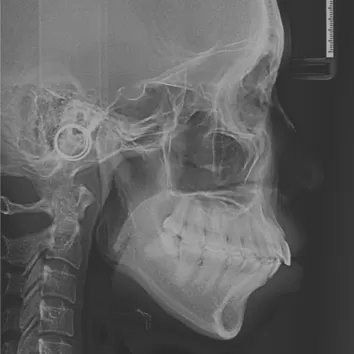

X-rays before treatment

[Panoramic Radiography/Lateral Cephalogram]